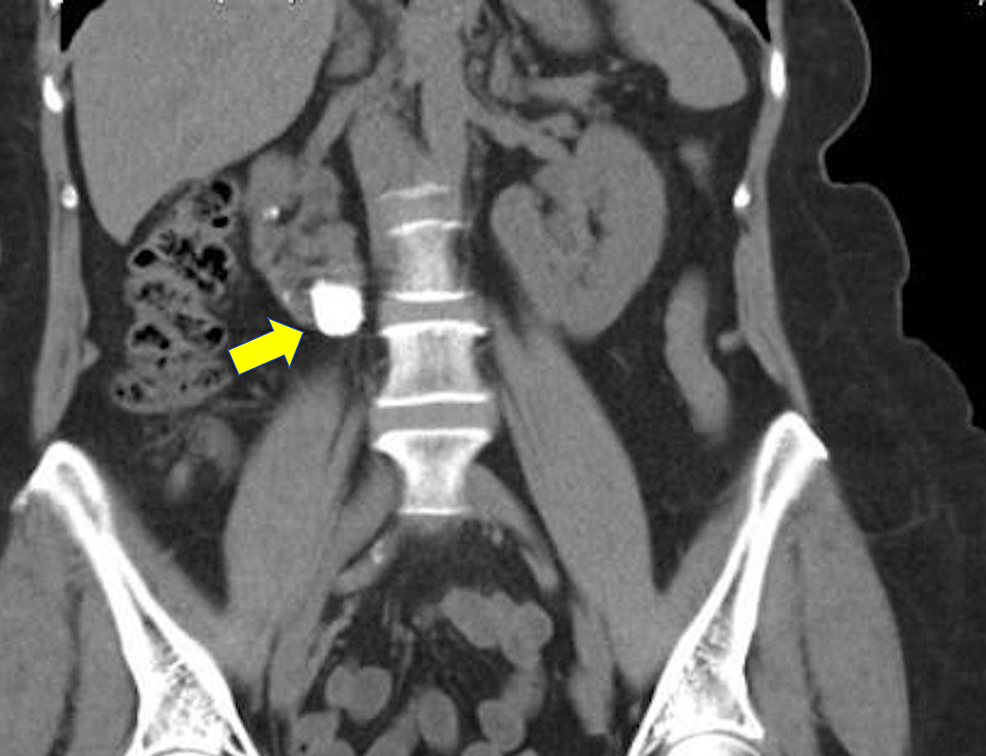

Figure 1 from Laparoscopic pyelolithotomy in a horseshoe kidney Horseshoe Kidney Laparoscopy Laparoscopic heminephrectomy is a feasible option in the surgical management of benign and malignant conditions of the horseshoe kidney and can be. Percutaneous, laparoscopic and robotic surgery can now be safely performed on horseshoe kidneys but require additional planning. Laparoscopic heminephrectomy is a feasible option in the surgical management of benign. Most horseshoe kidneys are asymptomatic, calculi, pelvic ureteric junction. Horseshoe Kidney Laparoscopy.